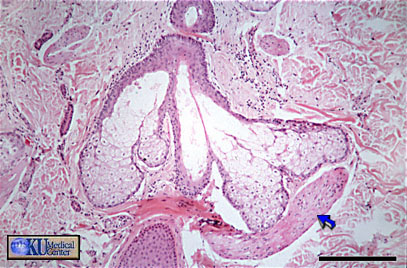

Sebaceous Gland = غدة دهنية